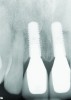

Fig 3. Radiograph confirming that the implant placement matched the presurgical plan.

Figure 3

Fig 4. Radiograph taken on the day of delivery of the final implant-supported restorations, 3 months after implant placement.

Figure 4

The DICOM (digital imaging and communications in medicine) images are then imported from the CBCT files into one of many commercially available implant-planning software programs. The surgeon and restorative dentist can then collaborate in choosing the precise position, angulation, and depth of implant placement, as well as the implant type, based upon a desired prosthetic outcome. Rosenfeld et al coined the term “collaborative accountability” to describe the pretreatment analysis and subsequent negotiated compromises between surgical and restorative colleagues on implant positioning and restorative design based upon anatomic limitations and the team’s willingness and ability to overcome them.3 Additionally, this pretreatment evaluation is invaluable in creating realistic patient expectations. Figure 1 through Figure 6 demonstrate a case showing 3-dimensional (3-D) presurgical planning, radiographic evidence of the plan’s execution, and 2-year follow-up. As a result of 3-D planning and subsequent guided implant surgery, the patient wound up with a pleasing, nature-like esthetic outcome (Figure 5).